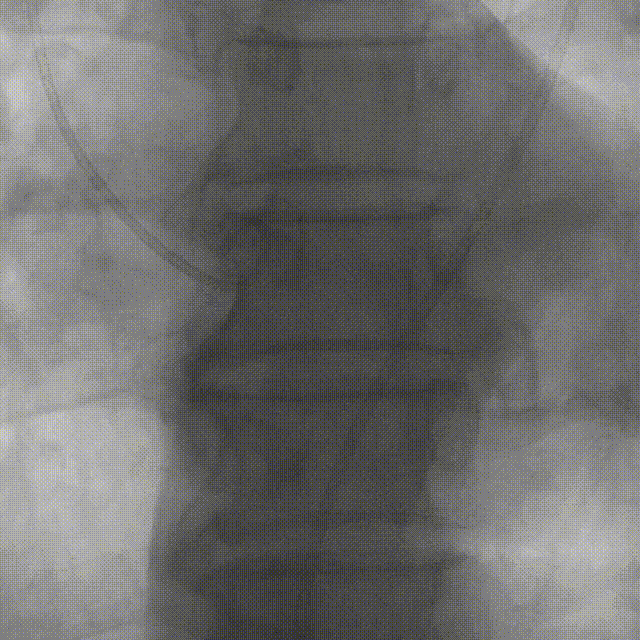

谷兴华教授 山东大学齐鲁医院 锚定终身获益,重视首次干预选择:心脏瓣膜病介入中心成立2年多来,中心核心目标始终保证在解决即刻病症的基础上,护航患者的全生命周期健康管理。 摆在眼前的实际是日益年轻化的患者群体,这意味着我们从手术伊始,就必须将患者未来数十年的生活质量和再次干预风险纳入核心考量,主动规划长远的健康路径。此次患者选择更具耐久的新型干瓣技术,力求减少患者未来再次干预的风险。同时,通过“TAVR+PCI一站式手术”这样的团队协作模式,系统性地处理多重心血管问题,避免分次手术的负担与风险,这正是我们中心一直秉持的“心脏瓣膜病全生命周期管理”理念的实践。让我们一起探索从“治已病”真正迈向“管长远”,让更多的患者获益! 病例特点速览 本次救治的患者,病情呈现“基础病交织、多病变叠加、锚定风险高”三大核心特征。患者为65岁,女性,病变特点TypeI型二叶瓣、轻度钙化,锚定风险大;同时患有冠状动脉粥样硬化性心脏病、慢阻肺(COPD);既往有长期吸烟饮酒史、脑梗死病史、高血压病史、乙肝小三阳病史及腹股沟疝修补手术史,患者STS评分9.32%,外科手术高危,经齐鲁医院瓣膜中心团队评估认为:局麻下“一站式TAVR+PCI”为最优治疗方案,结合患者较年轻,可选择具有长期耐久性的干瓣。 患者病史 主诉:活动后胸闷、憋喘余,加重20余天 既往史:30年前确诊乙肝小三阳,否认其他传染病史;有右腹股沟疝修补手术史,高血压病史,近期规律服药控制。 现病史:患者1年前出现活动后胸闷、憋喘,休息可缓解,为进一步诊治。2月前因“突发意识模糊、口齿不清”于当地医院入院,诊断为“急性脑梗死”,予以微创介入取栓治疗,恢复可,未遗留后遗症。20天前于当地医院再次入院行脑血管支架植入术,术后出现胸闷、憋喘,伴大汗,行心脏超声提示主动脉瓣重度狭窄,并行冠脉造影检查,予以药物治疗。10天前就诊于我院复查心脏超声提示二叶式主动脉瓣,主动脉瓣狭窄(重度)并反流(轻度)。患者现仍感胸闷,双上臂疼痛不适,咳嗽咳痰,日常活动受限。为行进一步治疗就诊于我院,门诊以“主动脉瓣狭窄、冠状动脉粥样硬化性心脏病”收入院; 个人史:吸烟50年,饮酒50年; 体格检查:体温:36℃,脉搏:67次/分,呼吸:18次/分,血压:143/76mmHg; 术前超声提示: 二叶式主动脉瓣主动脉瓣狭窄(重度)并反流(轻度);升主动脉扩张、左心扩大三尖瓣反流(少量);左室充盈异常;CW测最大压差86mmHg,平均压差43mmHg,最大血流速度463cm/s,连续方程法估测主动脉瓣口面积0.78cm² 术前CT评估 Type1型二叶瓣,轻度钙化、左右融合,主动脉瓣环径25.3mm,LVOT直径25.5mm,鱼嘴空间约26.6mm,主要靠瓣环锚定。窦部空间大、左右融合,VTC空间足够,无冠脉风险 ;左室内径正常,主动脉瓣环水平夹角49.6°。外周双侧入路内径可,髂外动脉存在散在钙化、双侧入路能够支持20F大鞘通过,右股低分叉,主动脉弓距弓角可。 个性化手术策略:局麻一站式方案+创新瓣膜精准适配 入路选择:主入路:右侧股动脉(右股分叉上方1cm处穿刺);辅入路:左侧股动脉;器械:20F大鞘; 手术流程规划:局麻下行同期一站式TAVR+PCI,植入ProStyle A®预装干瓣; 瓣膜选型与预处理:瓣膜型号:ProStyle A® AV32;不预扩; 定位与释放方案:初始定位:瓣上3mm处释放,瓣膜自然下滑至工作位,最终目标“0-瓣下5mm位”。 手术过程:局麻一站式操作+创新瓣膜植入,无缝衔接 手术团队按预设方案稳步推进,实现TAVR、PCI与ProStyle A®干瓣植入的无缝衔接: 1.术前准备:完成影像评估、血管通路建立,确认ProStyle A® AV32瓣膜状态; 2.PCI治疗:通过主入路完成左冠造影,前降支、对角支明显狭窄,精准植入两枚支架,恢复冠脉血供; 左冠造影,前降支、对角支病变 PCI后造影,病变血管充盈良好 3.主动脉根部造影:确认主动脉根部解剖结构,并精准跨瓣; 主动脉根部造影 精准跨瓣 4.干瓣植入:将瓣膜输送过弓、过瓣,并精准定位; 输送系统柔顺过弓 精准定位 5.术中评估:释放瓣膜至工作状态,再次造影评估,位置满意,完全释放瓣膜; 工作位评估 32号瓣膜稳定脱钩 6.释放后造影:可见瓣膜位置满意、形态良好,无明显瓣周漏。 最终造影,位置形态良好,无瓣周漏 术后超声探查:位置(瓣下4mm)、形态良好,无瓣周漏,PGmean=10mmHg。 此次手术的成功,体现了山东大学齐鲁医院心脏瓣膜病介入中心秉承的“心脏瓣膜病全生命周期管理”的理念和团队协作的临床能力。面对低龄高风险复杂病例,团队通过术前充分评估、术中精细操作,结合具有长期耐久性的干瓣技术,以一站式方案改善患者症状、提高生活质量并延长寿命,为类似病例的诊疗提供宝贵经验。 专家简介 谷兴华 山东大学齐鲁医院(点击查看专家详细简历)